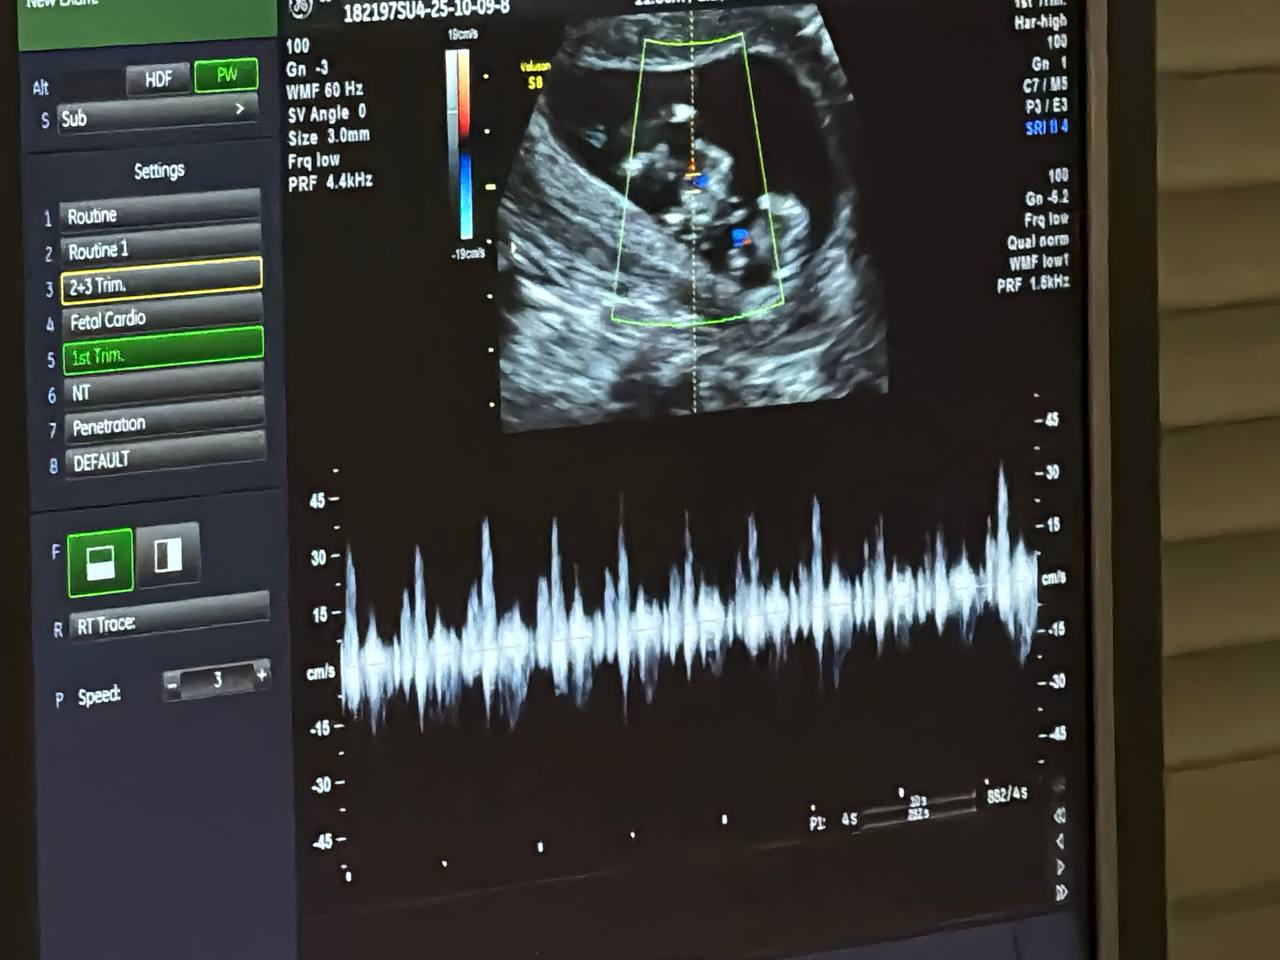

Под пристальным вниманием врачей в центре — многоплодные беременности. Екатерина из Кологрива приехала на обследование вместе с супругом. Доехали хорошо, дорога до областного центра, да и в целом, по региону, теперь в отличном состоянии, рассказала семейная пара губернатору. Вместе с будущими родителями глава региона послушал, как бьются сердечки малышей. Есть вероятность, что двойняшки будут однополыми, отметил врач ультразвуковой диагностики Владимир Хохолин.

Ежегодно в регионе проводится более шести тысяч скрининговых исследований, которые позволяют выявлять патологии на ранних сроках. Комплекс мероприятий в первом триместре беременности включает биохимический анализ крови на маркеры хромосомных аномалий и комплексную оценку здоровья мамы, рассказала главврач роддома Анна Федоренко. Исследование проводится в медико-генетической лаборатории.

«У нас есть необходимое оборудование. Анализатор проводит биохимию основных показателей. После результаты вместе с результатами УЗИ загружаются в специальную программу, которая рассчитывает возможные риски. Это позволяет своевременно профилактировать осложнения и снизить инвалидизацию деток», — пояснила биолог Юлия Замбржицкая.